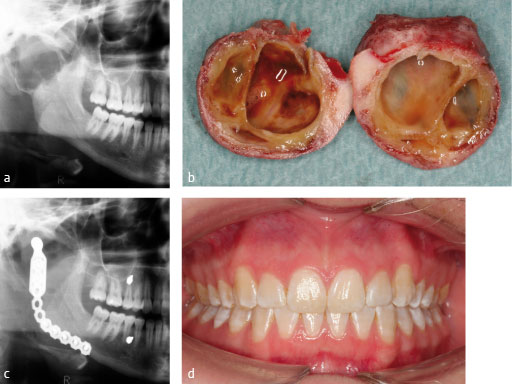

Figs 1ad: Resection of condyle and reconstruction with condylar add-on mounted on 2.4?mm reconstruction plate.

Case images courtesy of Oliver Driemel, Regensburg, DE